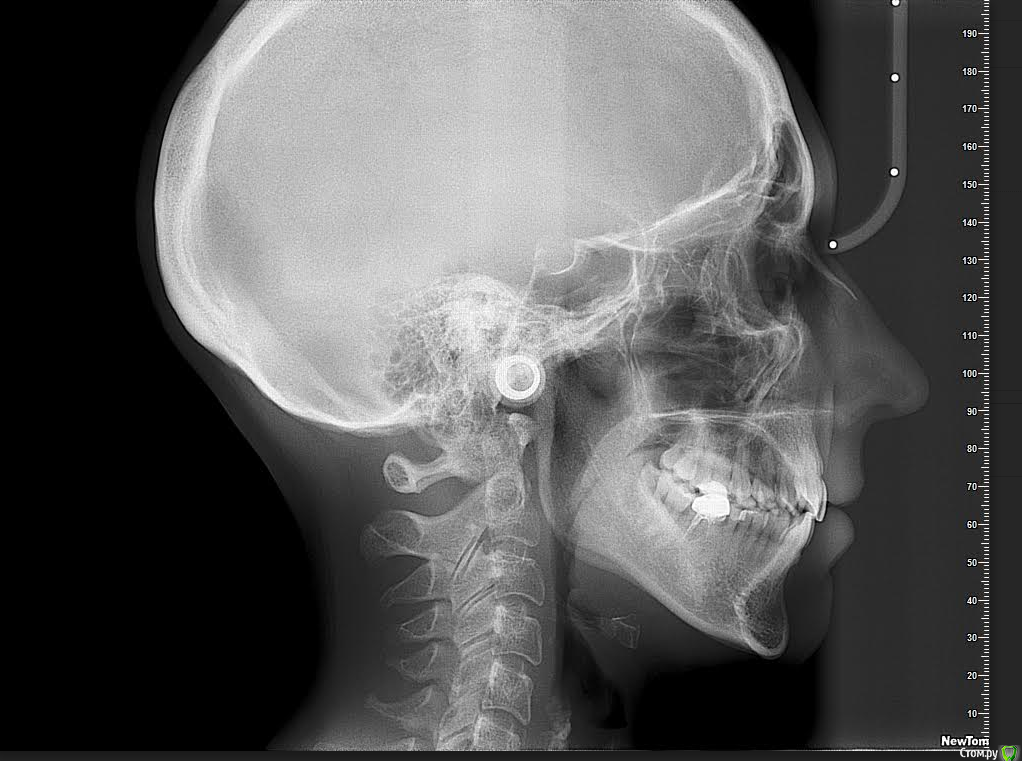

Мне 31 год. В детстве мне выбили верхний зуб 2-ку. Собираюсь лечиться брекетами, а потом вставлять имплант на место двойки. Но у меня есть еще проблеми с ВНЧС (с детства болит, хруст, щелчки), делала недавно КТ ВНЧС, диагноз артрит или артроз. Ходила к многим специалистам, все говорят разное. Надо ли проводить лечения капой моей дисфункции ВНЧС до установки брекетов или после установки брекетов?